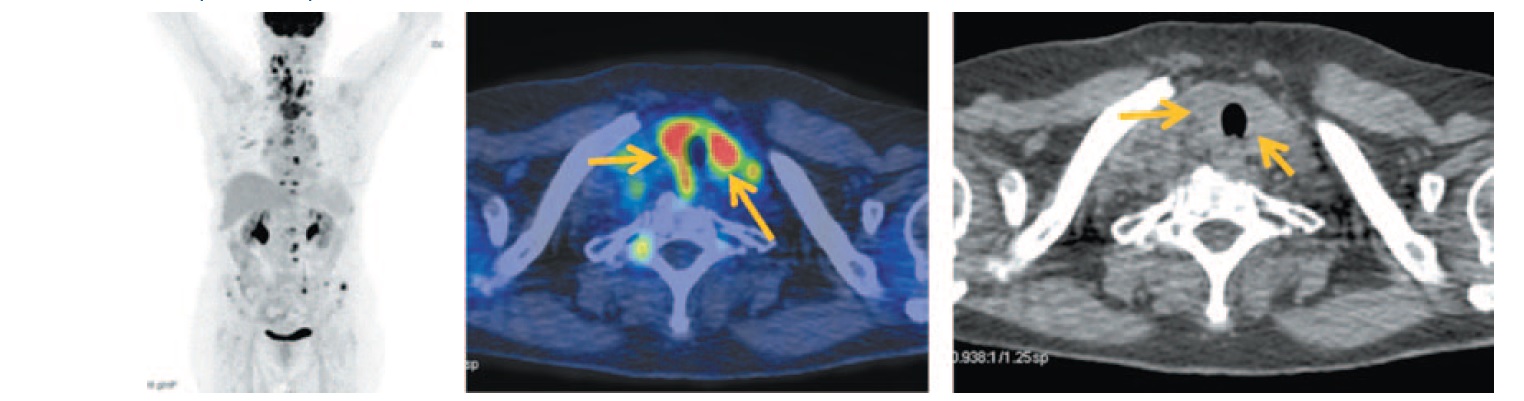

На MIP ПЭТ/КТ и аксиальных проекциях отмечается диффузное умеренное увеличение размеров щитовидной железы с повышенной фиксацией 18-ФДГ, коэффициент стандартизированного максимального накопления 18-ФДГ SUVmax составил 10,90. Структура ее однородная. С двух сторон отмечаются шейные лимфоузлы размером 8–13 мм с повышенной фиксацией радиофармпрепарата (РФП); рис. 1.

Рис. 1. Больная Б., 72 года, до лечения. На MIP и аксиальных ПЭТ/КТ проекциях отмечается диффузное умеренное увеличение размеров щитовидной железы: правой доли до 10×21 мм, левой доли до 13×22 мм с повышенной фиксацией РФП, SUVmax 10,90. Структура ее в условиях нативного сканирования однородная. Определяются лимфатические узлы с двух сторон размером до 8 мм SUVmax 5,48; IIa, IIb группы справа и III, IV групп с двух сторон размером до 13 мм с повышенной фиксацией РФП, SUVmax 12,93. / Fig. 1. A 72-year-old woman before the treatment. MIP and axial positron emission tomography/computed tomography (PET/CT) images show moderate diffuse enlargement of the thyroid gland: the right lobe of the thyroid gland is 10×21 mm, the left lobe of the thyroid gland is 13´22 mm with increased uptake of radiopharmaceutical, SUVmax 10.90. The structure of the thyroid gland during native computed tomography images was homogeneous. The images showed lymph nodes on both sides measuring 8 mm SUVmax 5.48; IIa, IIb groups on the right side and III, IV groups on both sides measuring 13 mm with increased uptake of radiopharmaceutical (RFP), SUVmax 12.93.